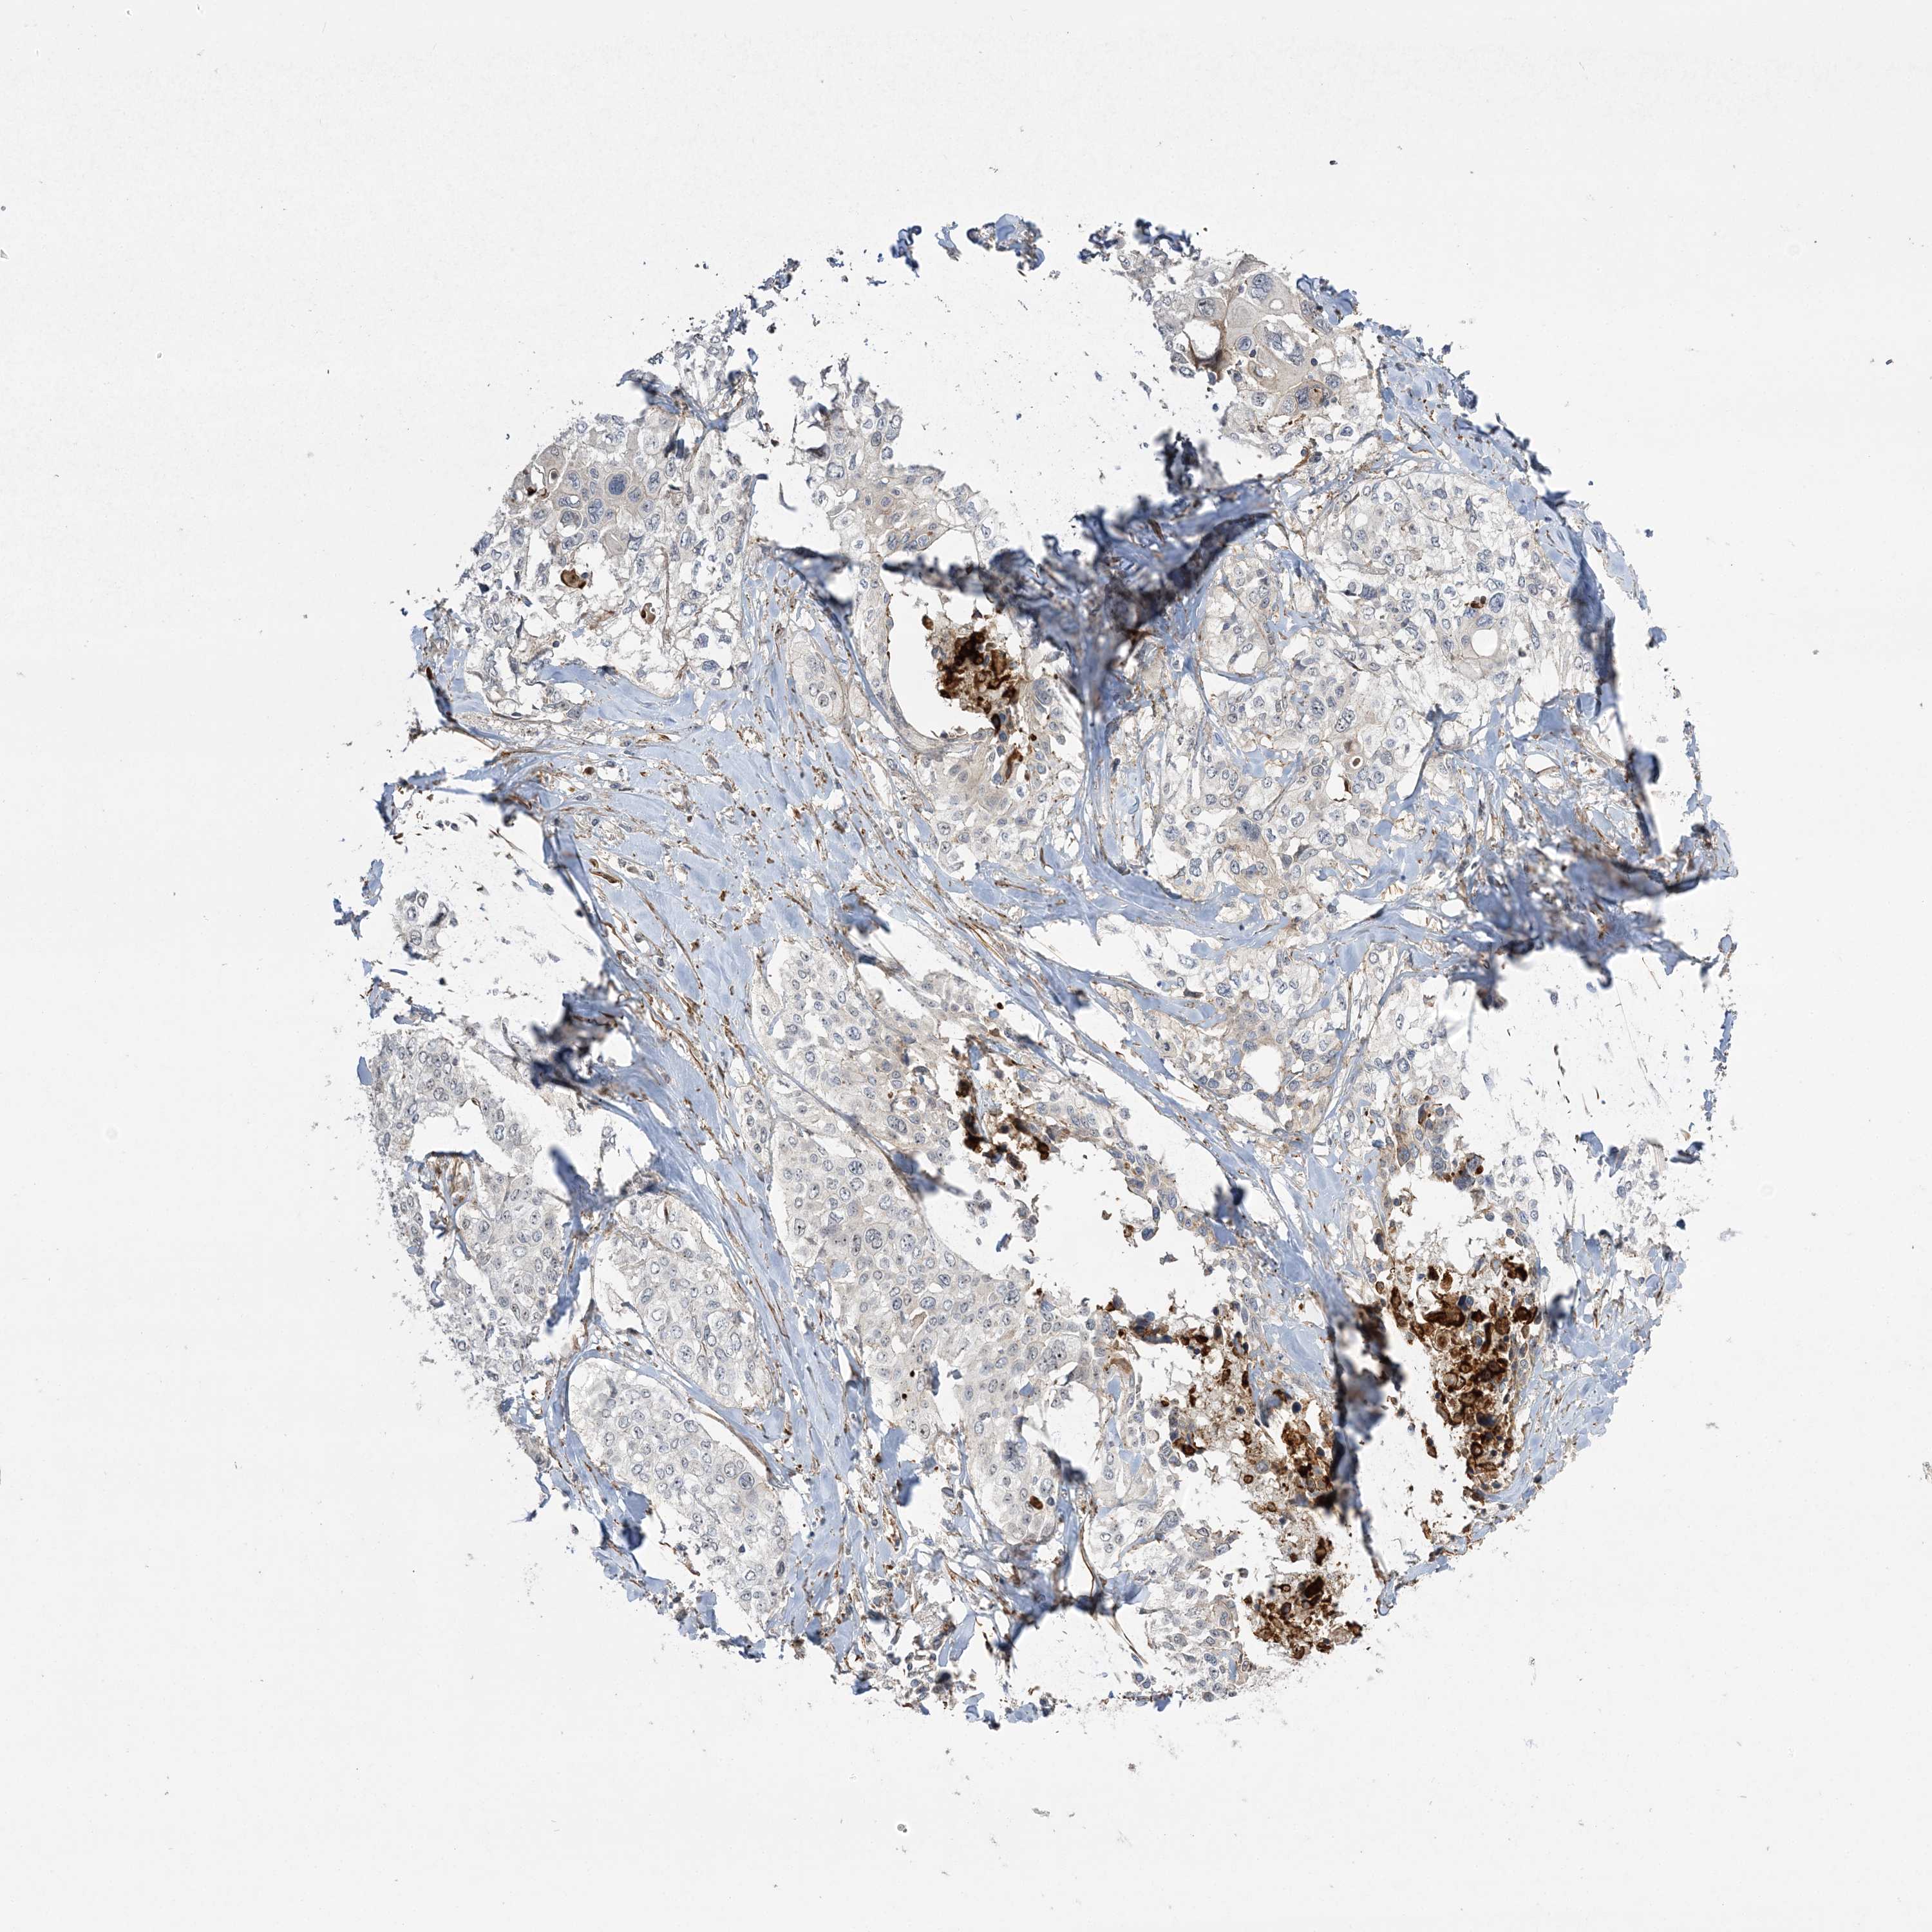

CERVICAL CANCER - Protein expressioni

A mouse-over function shows sample information and annotation data. Click on an image to view it in a full screen mode. Samples can be filtered based on level of antibody staining by selecting one or several of the following categories: high, medium, low and not detected. The assay and annotation is described here.

Note that samples used for immunohistochemistry by the Human Protein Atlas do not correspond to samples in the TCGA dataset.

Antibody stainingi

Antibody staining in the annotated cell types in the current human tissue is reported as not detected, low, medium, or high, based on conventional immunohistochemistry profiling in selected tissues. This score is based on the combination of the staining intensity and fraction of stained cells.

Each image is clickable and will lead to virtual microscopy that enables deeper exploration of all samples and also displays staining intensity scores, fraction scores and subcellular localization as well as patient and tissue information for each sample.

Antibody HPA036295

Antibody HPA036296

Staining

High

Medium

Low

Not detected

Intensity

Strong

Moderate

Weak

Negative

Quantity

>75%

75%-25%

<25%

None

Location

Nuclear

Cytoplasmic/membranous

Cytoplasmic/membranous,nuclear

Squamous cell carcinoma, NOS

Adenocarcinoma, NOS